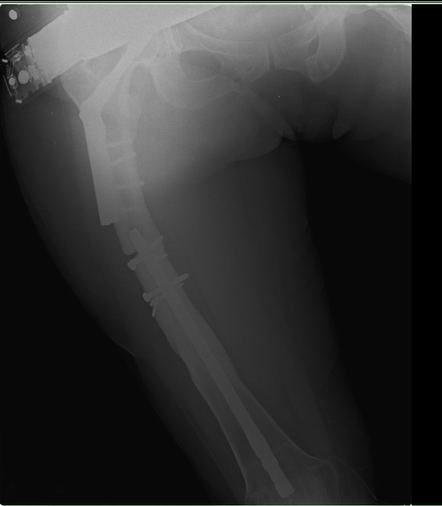

Уважаемые коллеги!Хочется услышать ваше мнение. Пациентка 48 лет, без вредных привычек, получила свежую травму (с\3 диафиза правого бедра) при падении с лестницы. Ранее (8 лет назад) была множественная травма, на бедре – перелом с\3, выполнен остеосинтез DFN Synthes (в др. ЛПУ). Перелом диафиза консолидировался очень медленно, от реостеосинтеза категорически отказывалась, в результате к 2 годам наступило сращение. Беспокоили боли при нагрузке, на рентгенограммах – зона разрежения вокруг кончика (проксимального) стержня и проксимальных винтов, согласилась лишь на удаление дистальных винтов для динамизации стержня. Пациентка пропала из поля зрения. Затем спустя 2 года при падении получает чрезвертельный перелом, выполнен остеосинтез бедренным винтом ( DHS ).Планирую удаление имплантов (кроме проволоки), рассверливание костно-мозгового канала (сейчас стоит гвоздь 10 мм, попытаюсь рассверлить до 14-15 диаметра, чтобы поставить 12 мм или 13 мм гвоздь), внутрикостный остеосинтез блокированным стержнем (динамически).

Теперь вопросы: 1.Так как нет оригинального инструмента Synthes , то интересует резьба на конце стержня какой диаметр и метрическая ли она. 2.Есть ли заглушка на стержне (мне так кажется, что нет). 3.Нужно ли заполнять полость аутокостью от шеечного винта. Извиняюсь за качество снимков. Спасибо! С уважением, А.Минервин.

Уважаемые коллеги! Кратко отчитаюсь по представленному случаю.

Вчера пациентка прооперирована. Как и ожидалось, основные трудности были с удалением металла. Удаление произведено из трех доступов: где пластина 8 см, блокирующие винты- 5 см, сам стержень 3 см.. Дольше всего пришлось извлекать end cap у стержня, далее сломался 1 винт в пластине (долото в помощь, но аккуратно, только наружный кортикал, из внутреннего - выкручен). Рассверлил дистальный отломок до 14 мм, проксимальный до 13 мм. Стержень ChM, диаметр12 мм. Долго существующая деформация бедра предопределила и положение стержня в проксимальном отломке – тесно к наружному кортикалу, надеюсь, до угрожающего конфликта не дойдет.

Спасибо всем участникам! Критика приветствуется J.

P.S. Резьба на стержне действительно М8. Если кому нужно, в сети есть брошюрка Synthes Nail Removal с указанием резьб.

С уважением, А.Минервин.